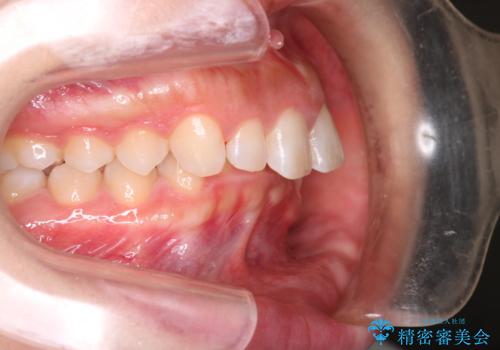

- 上の前歯の出っ歯と前歯の深い咬み合わせを治したいとのことで来院された患者様です。

上顎の歯は後方移動とIPR(歯と歯の間を削る)によって口元が引っ込むように、下顎は歯列全体の拡大とIPRによって上顎とバランスよく咬み合うように設計し、インビザラインにより治療を行うこととしました。

上顎歯列の後方への移動量が多く、右側の奥歯の咬み合わせを改善する必要もあったため、治療には長期間を要しました。